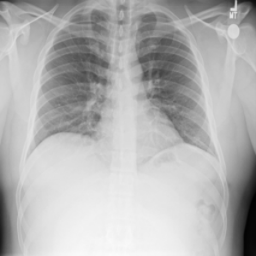

To validate the zero-shot and weakly supervised segmentation results, as well as different design components of the MedCLIP-SAM framework, we used three public datasets (three different modalities) with segmentation ground truths (segmentation of breast tumor, brain tumor, and lung), which were split for training, validation, and testing. These datasets with their divisions include:

• Lung Chest X-ray: COVID-19 Radiography Database (COVID-QU-Ex) [11, 27] with 16,280, 1,372, and 957 Chest X-ray scans (normal, lung opacity, viral pneumonia, and COVID-19 cases) for training, validation, and testing.

In Table 3, we present segmentation accuracy for our proposed method in zero-shot and weakly supervised settings, with fully supervised segmentation as a reference. Note that for zero-shot results, we include a comparison between initial labels generated by gScoreCAM-based saliency maps (“Saliency Maps”) and pseudo-masks from SAM (“Saliency Maps + SAM”). Combining BiomedCLIP and SAM demonstrates clear advantages, notably improving segmentation quality for all metrics (p<0.05𝑝0.05p<0.05). Comparing zero-shot results to weakly supervised segmentation, we observe general improvements for X-ray-based lung segmentation. However, the impact on tumor segmentation in breast ultrasound and brain MRI remains unclear, with an AUC boost of similar-to\sim2% only for breast ultrasound. While fully supervised DL models currently provide state-of-the-art accuracy for medical image segmentation, our MedCLIP-SAM zero-shot segmentation outperformed ResUNet-based full supervision for breast ultrasound and brain MRI segmentation. Lung X-ray segmentation, however, showed superior accuracy with the fully supervised method across all metrics. Finally, to provide a qualitative assessment, exemplary segmentation results for zero-shot and weakly supervised settings are shown in Fig. 2 against the original image and ground truths (GTs) across all segmentation tasks.